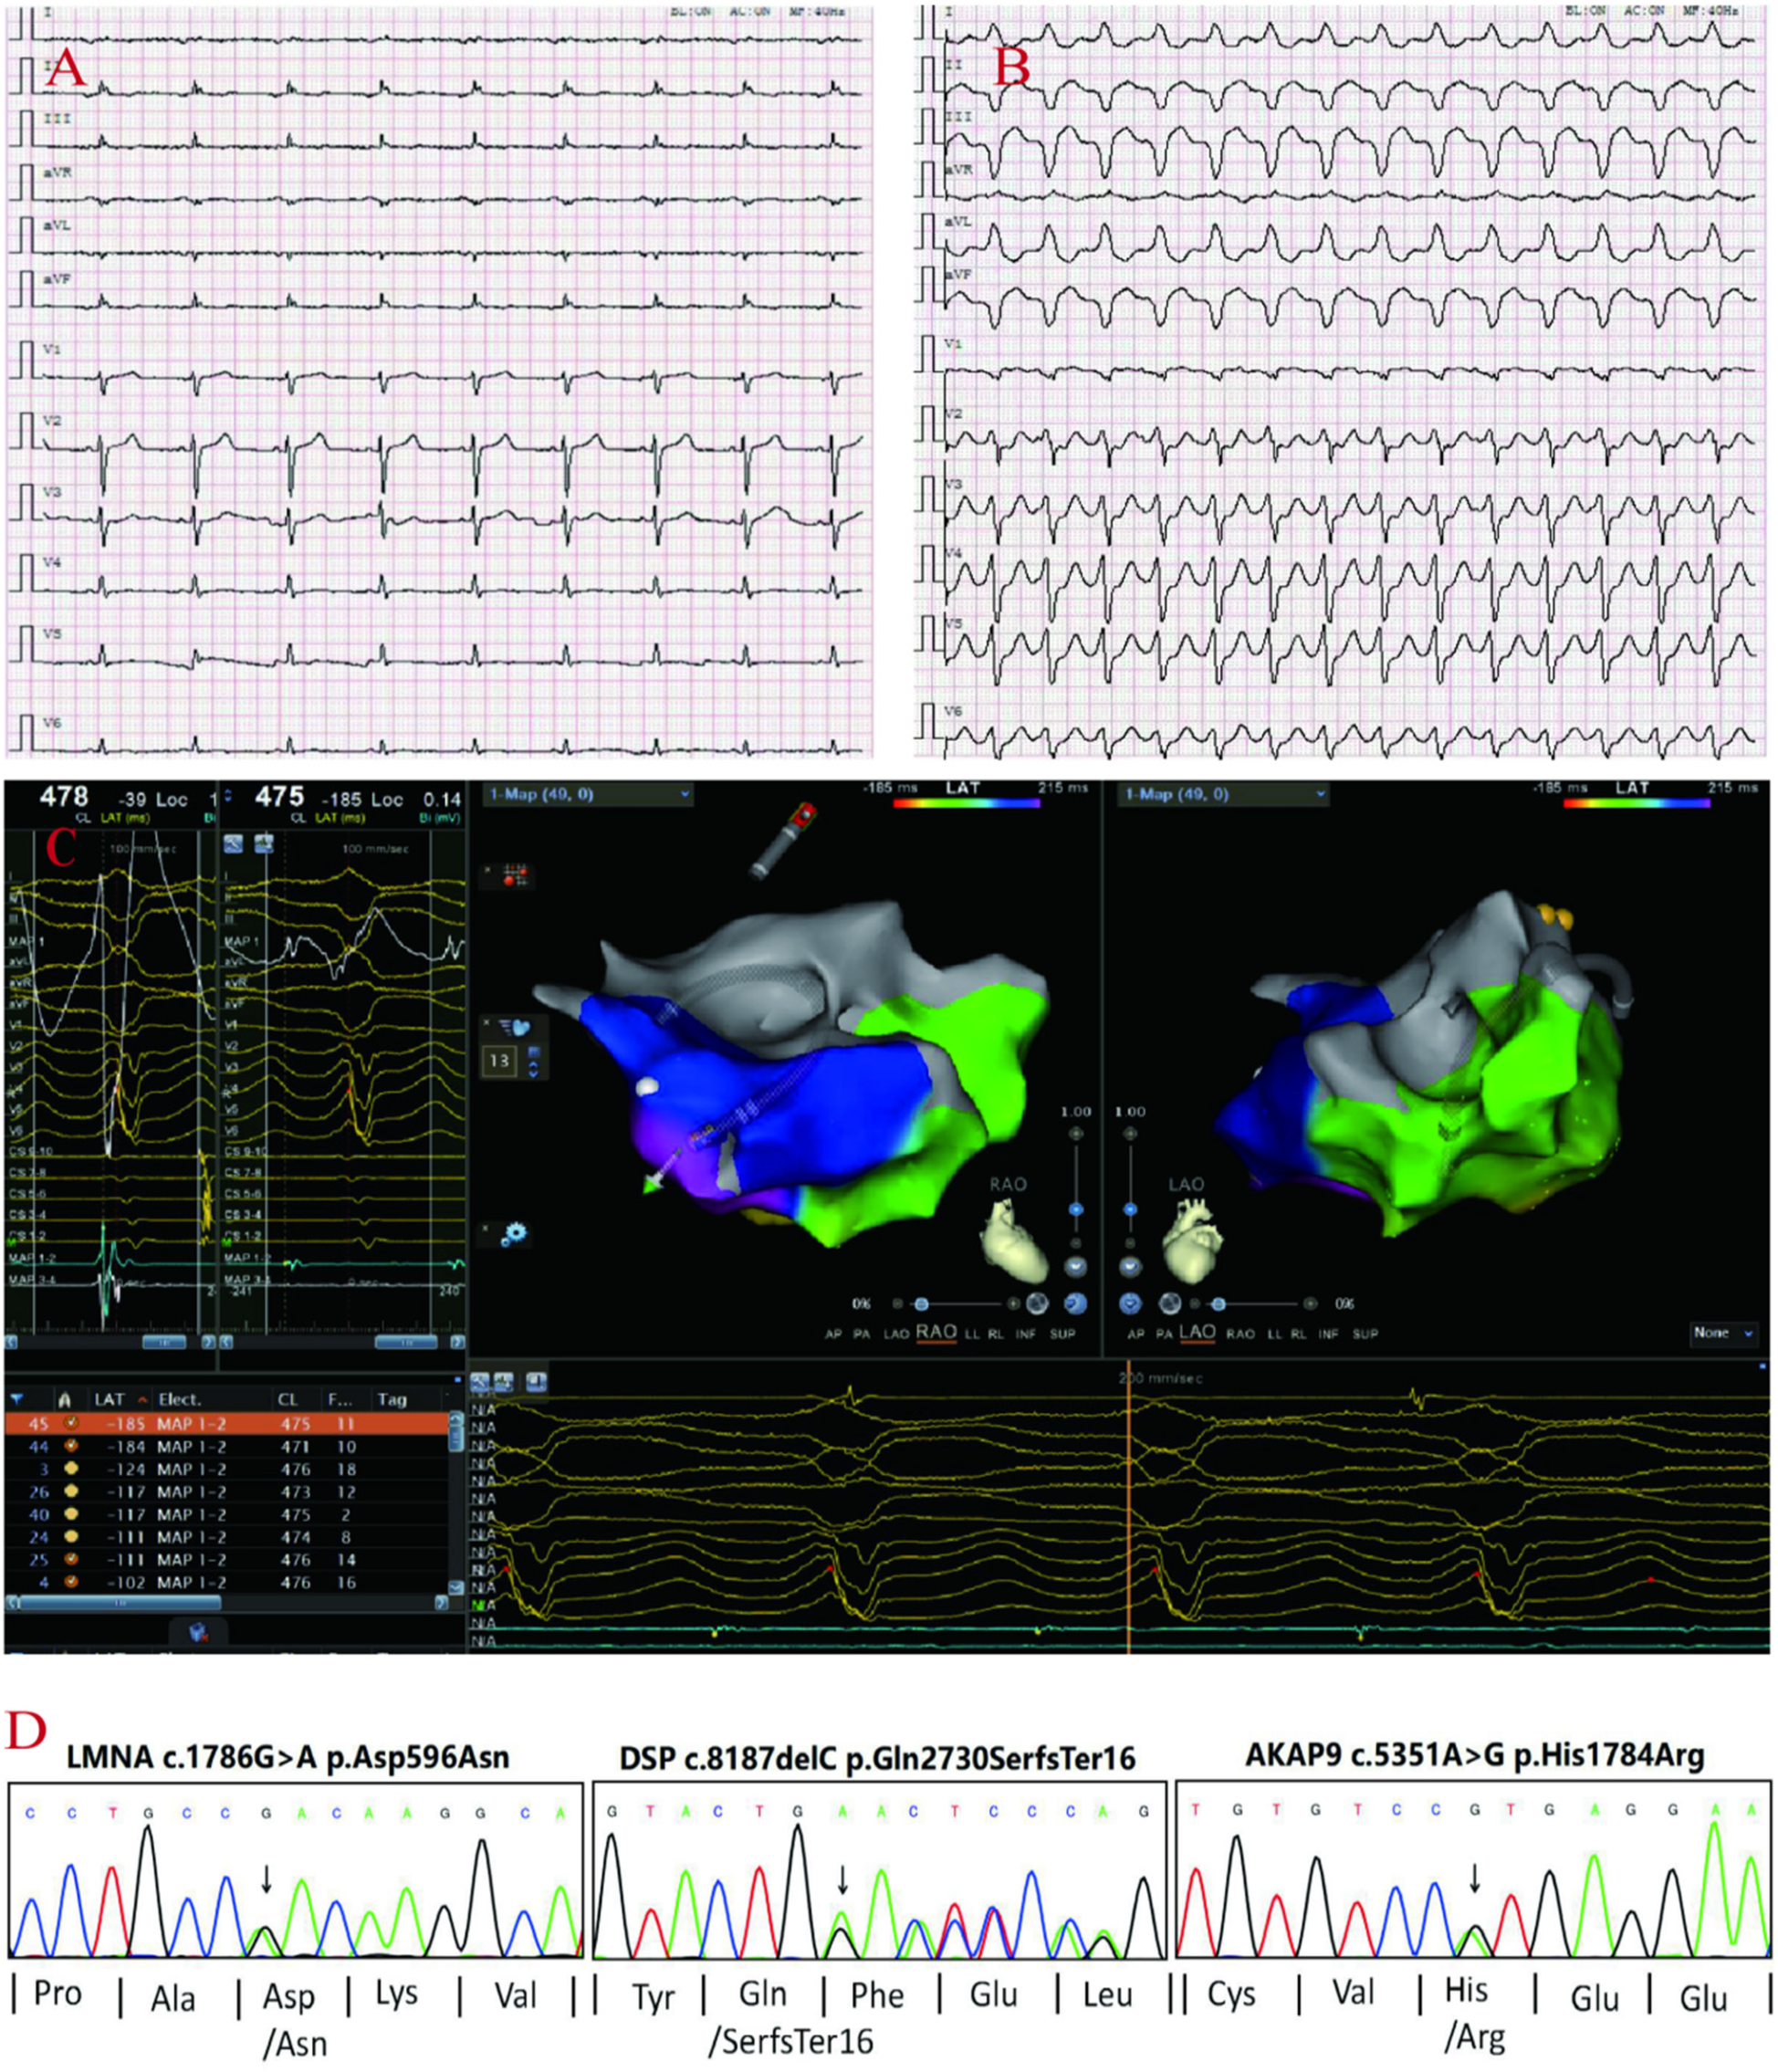

A 71-year-old male patient (proband) presented to the hospital with recurrent sudden syncope, and comprehensive evaluation revealed that his electrocardiogram revealed a prolonged Q-T interval, low-voltage QRS complexes in the limb leads, and multiple episodes of nonsustained ventricular tachycardia (QRS complexes with left bundle branch block morphology) (Figures 1A–C); echocardiography and magnetic resonance imaging revealed global enlargement of the left and right ventricles, global hypokinesia, multiple thinning of the ventricular wall, ventricular aneurysm in the right ventricle (regional myocardial paradoxical movement), widening of the right ventricular outflow tract, and decreased left and right ventricular ejection fractions (Figures 2A,B,D,E); magnetic resonance enhancement (LGE) revealed subepicardial free walls in the middle left ventricle, interventricular septal wall, and transmural myocardial fibrosis images in the right ventricular inferior wall (Figures 2C,F) (Supplementary Material S1), and coronary angiography revealed plaque formation in the proximal left anterior descending artery, 30% stenosis, and no significant stenosis in the remaining vessels. In view of the proband's clinical manifestations and multimodality imaging results, we suspected that he had ACM and performed whole exome sequencing (WES): DNA was first extracted from peripheral blood, libraries were constructed using Agilent SureSelectXT V6, and sequenced on the Illumina NovaSeq 6,000 platform.Data analysis was screened by BWA alignment (GRCh37/hg19), PICARD de-duplication, SnpEff and ANNOVAR annotation, focusing on exonic regions and non-coding variants affecting splicing (Splice-AI > 0.2), combined with disease database and Shengxin software prediction. The pathogenicity of genetic variants was judged according to the American College of Medical Genetics and Genomics (ACMG) and Association for Molecular Pathology (AMP) criteria (9), the results revealed that he carried three rare mutations: the heterozygous missense variant c.1786G > A (p.Asp596Asn) in the LMNA gene(suspected causative), the heterozygous variant c.8187delC (p.Gln2730SerfsTer16) in the DSP gene(suspected causative), and the heterozygous missense variant c.5351A > G (p.His1784Arg) in the AKAP9 gene (unknown significance) (Figure 1D). All variants were verified by Sanger sequencing, and co-segregation analysis was performed on family members. The proband was diagnosed with arrhythmogenic biventricular cardiomyopathy and Q-T interval prolongation according to the revised 2020 ITF diagnostic criteria for ACM and was considered to have a high risk of malignant arrhythmia and sudden death. Radiofrequency ablation and drug therapy were performed after consultation with the proband and his family members, considering the hereditary nature of the disease, we conducted genetic testing and comprehensive evaluations for the proband's family members.

Figure 1

proband's ECG: Q-T interval prolongation, low voltage of QRS complex in limb leads (A), non-persistent ventricular tachycardia (QRS group with left bundle branch block pattern) (B). Electrophysiological: the earliest V wave measured in the chamber speed state (C). Sanger sequencing confirmed the the variants in DSP, AKAP9, LMNA genes in the proband (D).